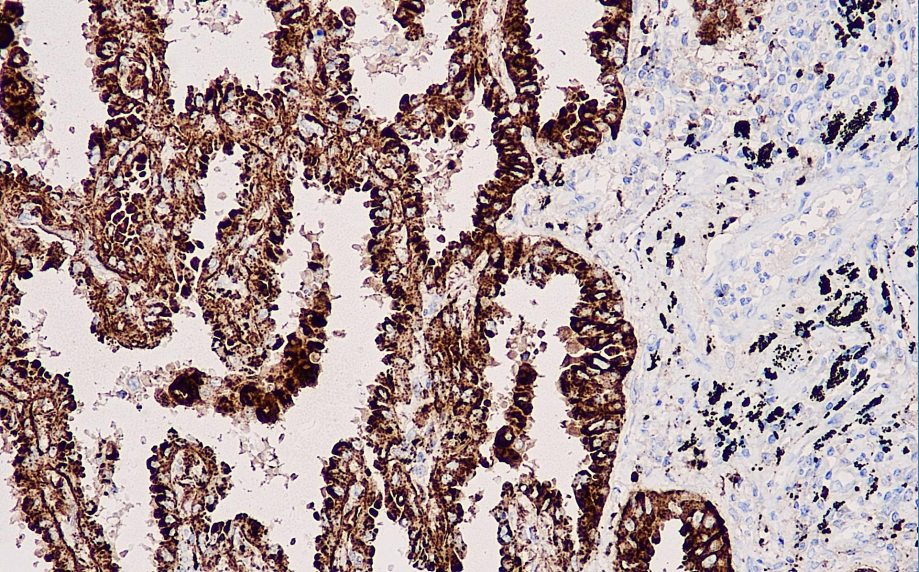

Positive control: Lung adenocarcinoma

NapsinA is A gastric enzyme-like aspartic acid protease, which is divided into two types: NapsinA and Napsin B. NapsinA is a single-chain protein with a molecular weight of approximately 38kDa. It is highly expressed in the lungs and kidneys and lowly expressed in the spleen. Napsin A is expressed in type II alveoli and lung adenocarcinoma. Its specific high expression in lung adenocarcinoma helps to distinguish lung adenocarcinoma from adenocarcinoma of other sources and other types of lung cancer.

Napsin A antibody reagent can specifically bind to the Napsin A molecular antigen. The immunohistochemical kit containing Napsin A antibody reagent is suitable for the precise diagnosis of lung adenocarcinoma and squamous cell carcinoma.